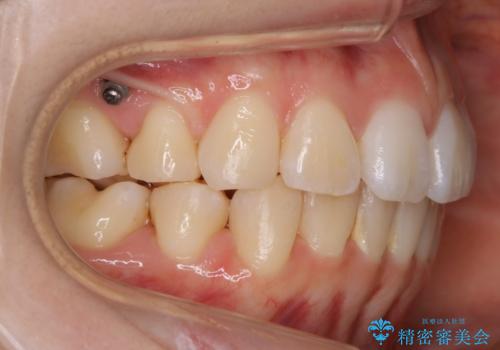

- 以前、中学生から高校生にかけてワイヤー装置による抜歯矯正を経験されている患者さんで、大人になってからのライフスタイルの変化でリテーナーを継続使用することができず、ガタつきが目立つようになってきてしまったのでもう一度矯正治療がしたいという主訴でご来院されました。

既に上下左右の4番目の歯が抜歯されているため、今回の治療では抜歯をせず歯の移動だけでガタつきを治す必要があり難易度が高くなっていました。

小学生~高校生の頃に一度矯正治療を経験している方も、その後の生活の変化の中でリテーナー(後戻り防止装置)の継続使用が困難となり、時間の経過とともにガタつきが再発現してしまうケースが多くあります。

最初の治療の時点で抜歯をしている場合や、ガタつきの度合いによっては再治療といえど初回の矯正治療と同じくらいの期間を要する場合もあります。